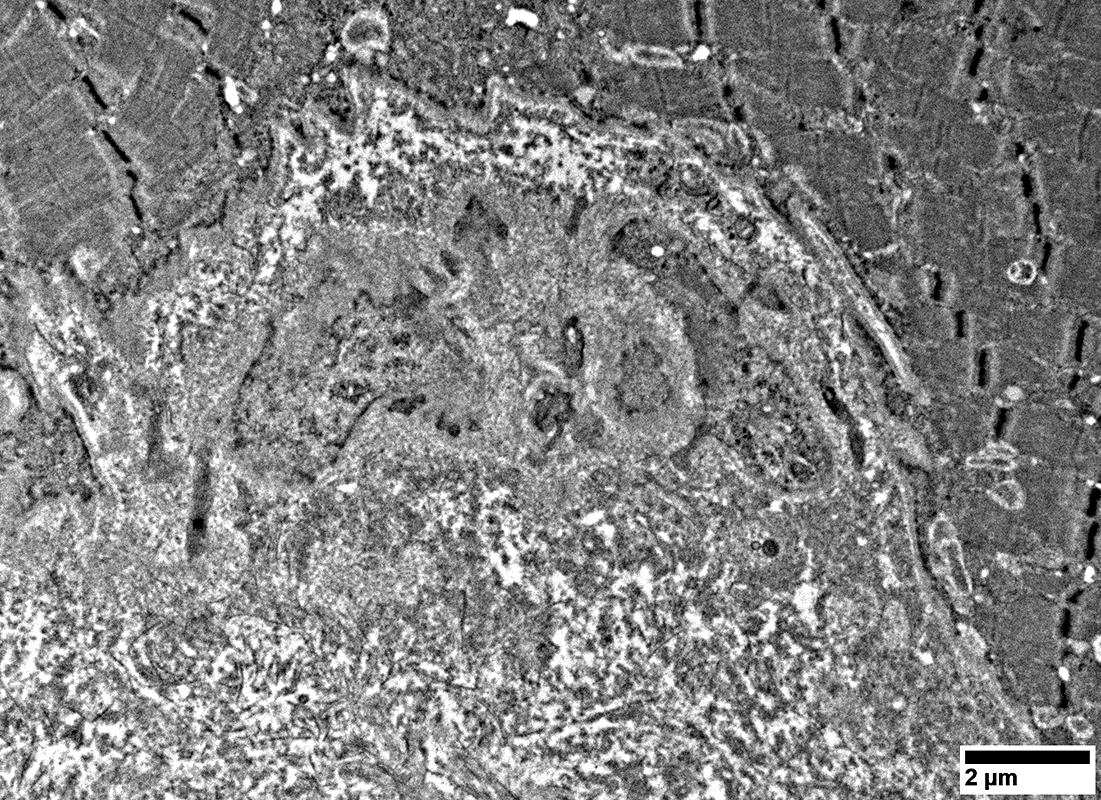

Capillaries

From: R Schmidt

Abnormal pericytes in capillary wall

Cell, probably lymphocyte, below capillary

Damaged endomysial capillary